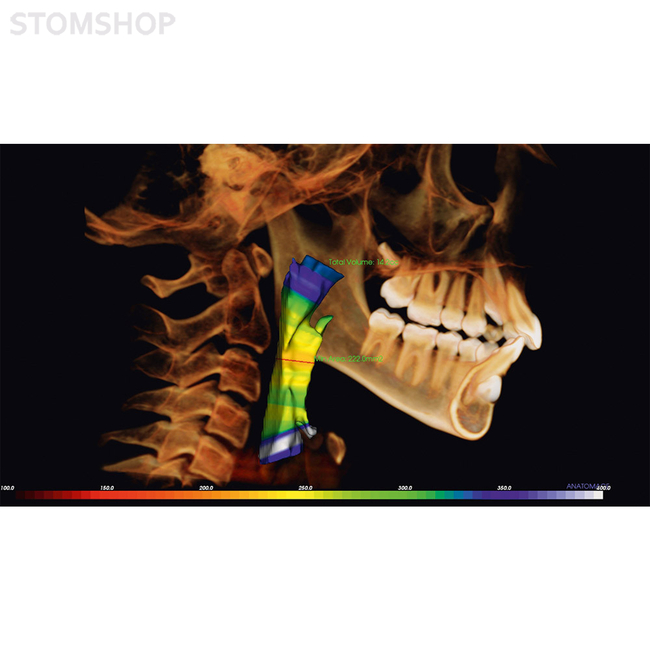

Исследование дыхательных путей: визуализация узких дыхательных путей

Имплантология: высокоточные планы имплантации

Эндодонтология: оценка корня зуба в трех измерениях

Ортодонтия: план лечения с повышенной точностью

Челюстно-лицевая хирургия и MJF (ротовая, лицевая, челюстная хирургия): определение характера хирургического вмешательства

Гнатология: индивидуальная диагностика нижней челюсти